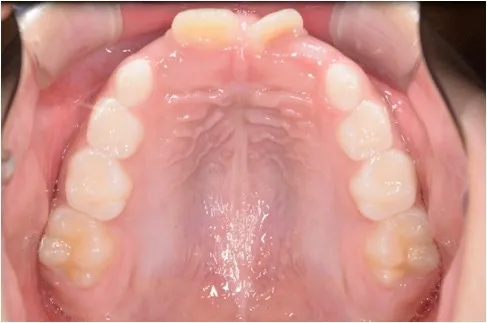

【治療前 上顎】